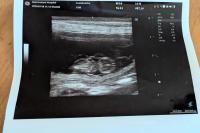

ニーナ受胎してました!

ニーナ妊娠エコー検査行ってきました、ニーナはつわりもなく受胎してるか半信半疑でしたが3頭受態確認できました❣

ニーナも初産なのでドキドキものです犬のお産は安産ではないので人の介助も必要です気を引き締めてお産に挑みますニーナの出産予定は8月中旬予定になります、お父ちゃんはジークです天使達無事生まれてきますように!